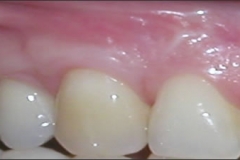

This mouth had recession on just one tooth with very little bone to support the tooth. The area needed support and thickness. The tissue was placed and the area now has thicker tissue to withstand the forces that the patient needs to place on it.